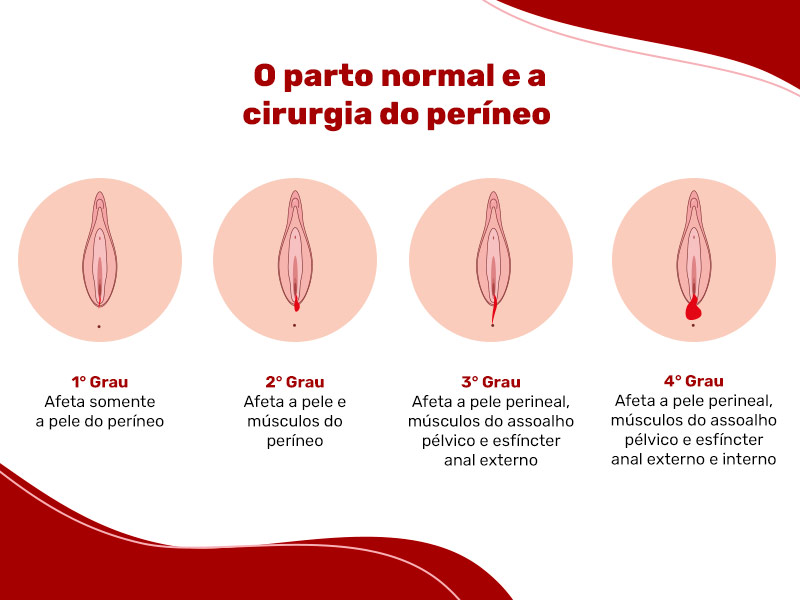

O parto vaginal é um dos principais fatores que podem afetar o períneo, causando distensões ou até lacerações. O envelhecimento e o excesso de peso também podem fragilizar essa musculatura.